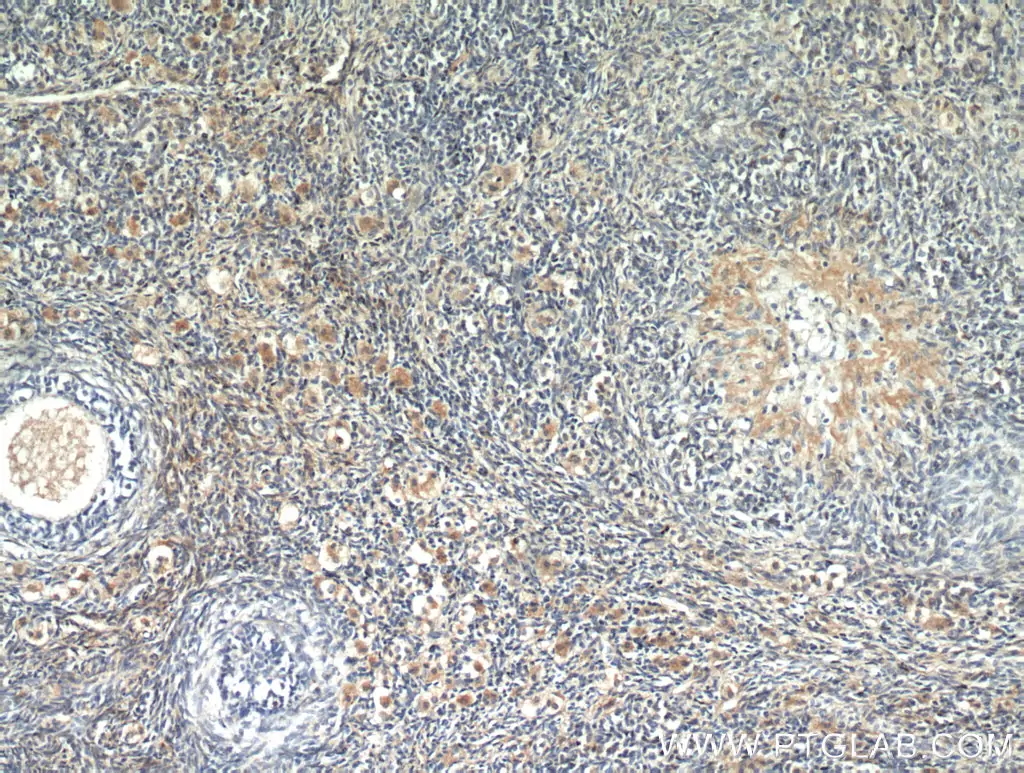

Fino ad ora il marcatore ematochimico più comunemente accettato a scopo diagnostico era il Ca 125, più recentemente è stato introdotto nella pratica clinica un nuovo marcatore di tumore ovarico denominato HE4 (Human Epididymis protein 4).

HE4 già come marcatore tumorale usato singolarmente si è dimostrato più sensibile  di Ca 125, soprattutto nel discriminare tra carcinomi ovarici e masse benigne.

Pertanto HE4, da solo o meglio in combinazione con Ca 125, si é rivelato uno strumento diagnostico in grado di aumentare la sensibilità nel discriminare tra patologia maligna e benigna, nella diagnosi precoce (1° e 2° stadio), nell’individuare le recidive e nel monitorare la terapia.